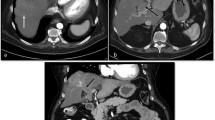

Multiphase CT is an option used to further characterize liver lesions noted on ultrasound or single-phase CT (Fig. 7.2). After the administration of intravenous contrast, CT scans are usually performed in the late arterial phase, portal venous phase, and delayed phase. The arterial phase is usually performed at 15–30 s [13] and represents the enhancement of the hepatic arteries with some early enhancement of the portal veins. The portal venous phase is performed at approximately 60–80 s and represents enhancement of the entire portal venous system as well as the hepatic veins [14]. A delayed scan is obtained at approximately 3–5 min and represents the equilibrium phase when contrast has mostly washed out of the liver parenchyma.

( a ) CT of the liver during the arterial phase demonstrates a lesion in the liver dome that is hyperenhancing relative to the rest of the liver parenchyma. ( b ) Venous phase demonstrates that the lesion is hypoenhancing compared to surrounding liver parenchyma. This is referred to as “washout.” There is a faint area of enhancement around the lesion, which is the pseudocapsule. ( c ) Delayed phase imaging demonstrates persistent washout of the lesion relative to surrounding liver parenchyma. ( d ) Initial single-phase scan obtained during the early venous phase, which better demonstrates the peripherally enhancing pseudocapsule. Collectively, this multiphase exam demonstrates characteristics highly suspicious for HCC, which are arterial enhancement, venous phase washout, and pseudocapsule formation